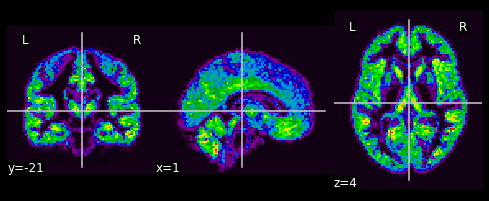

Plot the barycenter itself#

def data_to_nii(x):

return nilearn.image.new_img_like(

gm_imgs[0], data=np.array(x.reshape(grid_size))

)

plotting.plot_epi(data_to_nii(barycenter.histogram))

plt.show()

SqEuclidean barycenter, for reference#

plotting.plot_epi(data_to_nii(np.mean(a, axis=0)))

<nilearn.plotting.displays.OrthoSlicer at 0x7f48503fb710>